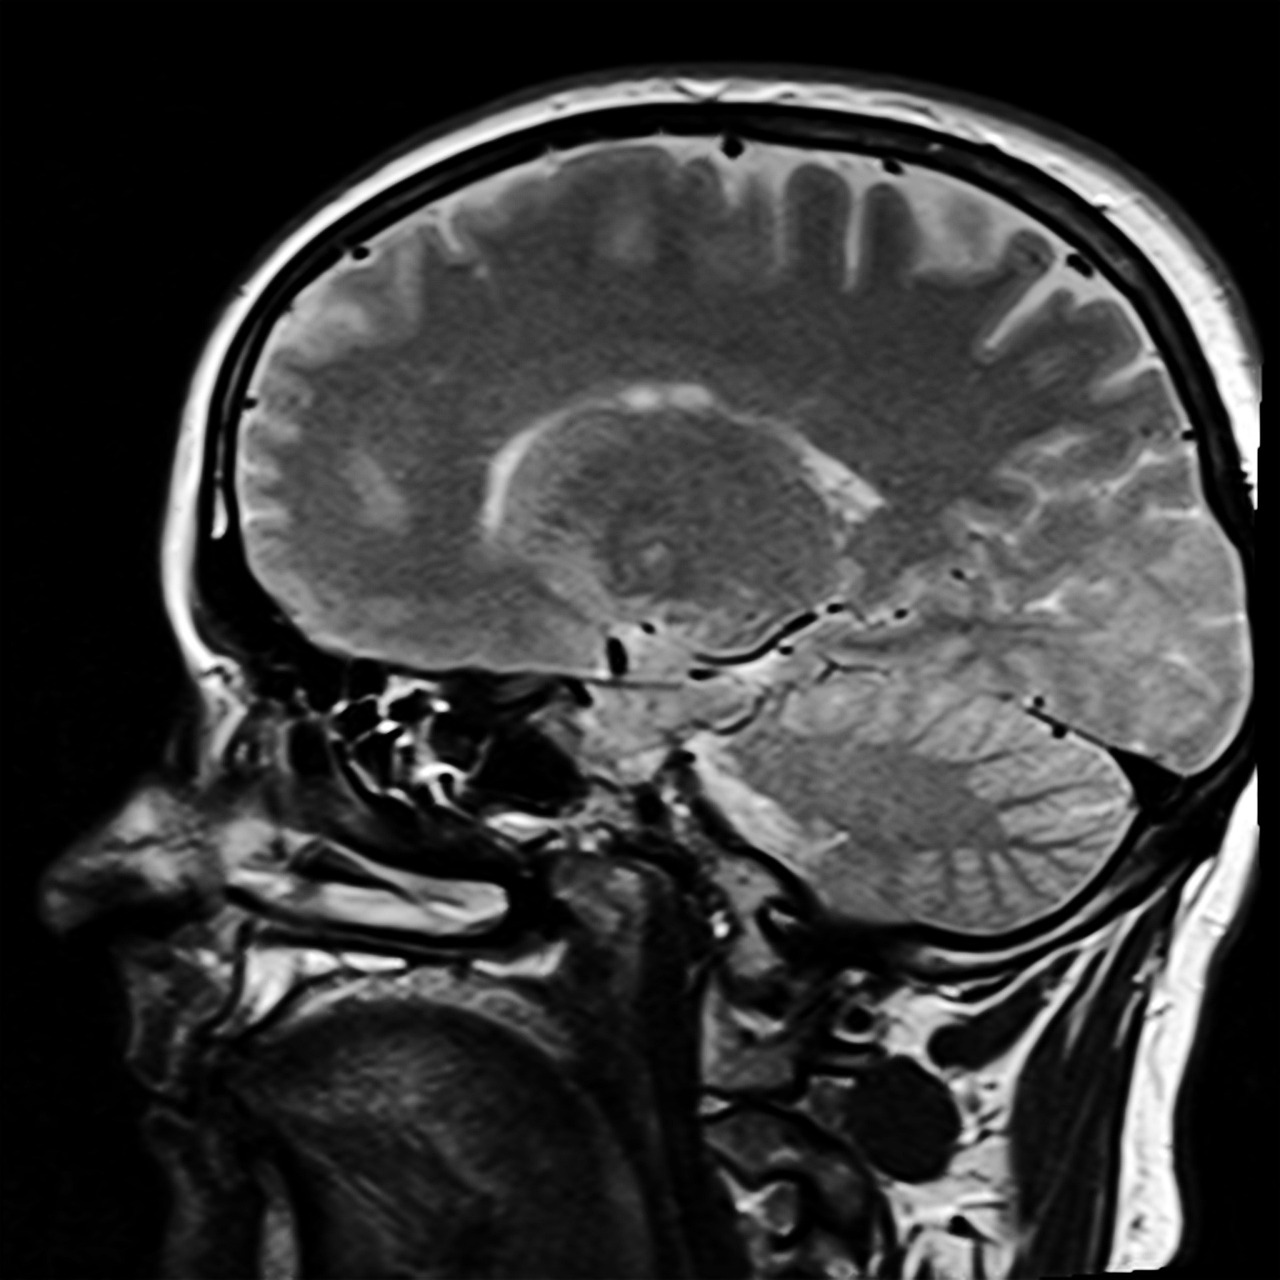

뇌수막은 뇌를 감싸고 있는 연질막과 연질막의 밖에서 뇌척수공간을 포함하고 있는 거미막과 바깥쪽에서 뇌와 척수를 보호하는 경질막으로 구성됩니다. 뇌수막염은 거미막과 연질막 사이에 있는 거미막 밑 공간에 염증이 발생하여 나타나는 질병입니다.